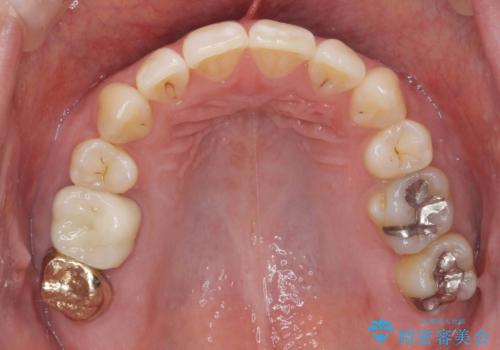

- 矯正装置

- ワイヤー矯正

- 前歯のがたつきを主訴に来院。

前歯のクロスバイト、上の前歯の正中が右にずれていました。

右上の奥歯の高さもない状態でしたが、矯正治療が終わってからしっかりかぶせました。

上下左右の小臼歯を抜歯しています。